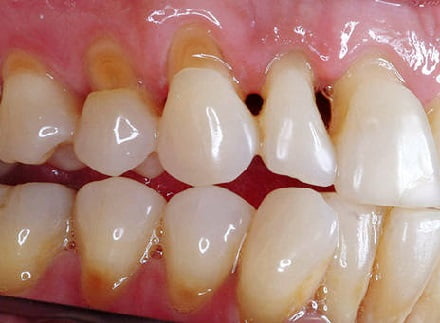

Пришеечный кариес: фото до и после

Как выглядит данный тип кариеса, предлагаем к просмотру подробные фото зуба.